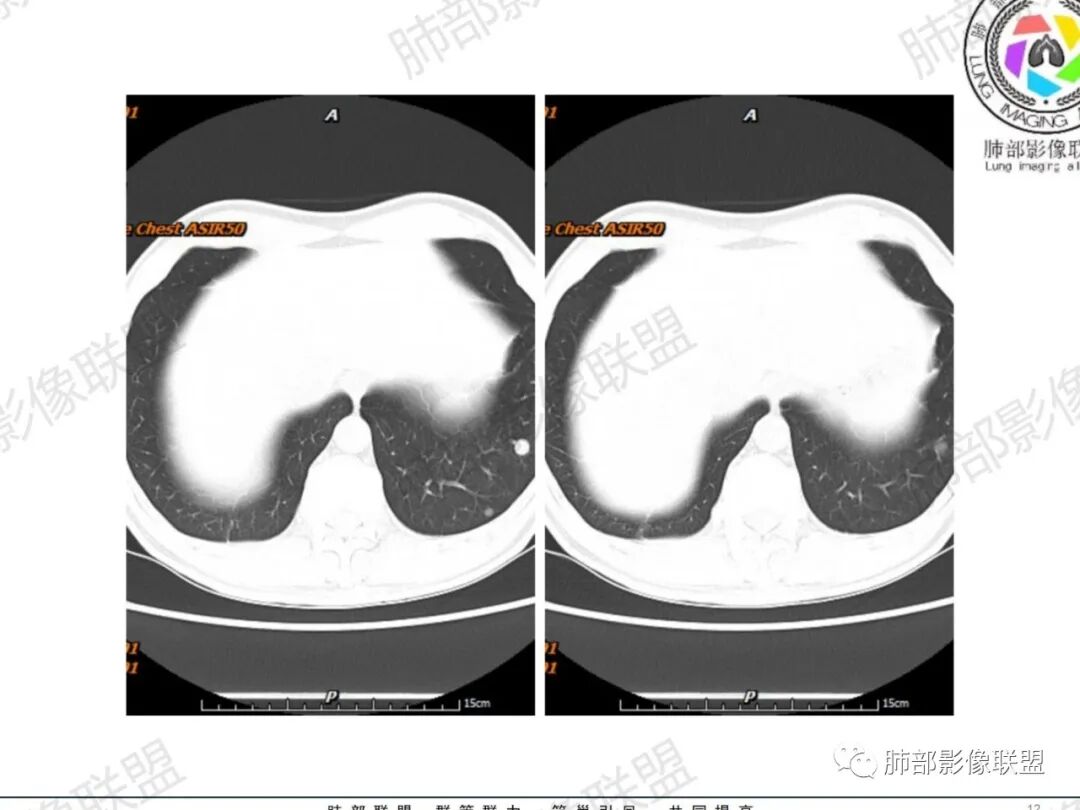

琦遇:恶性没有问题,肺气肿底子、病灶分叶、少许毛刺、叶间胸膜凹陷、部分边缘可见清晰的GGO、胸膜牵拉凹陷、局部胸水、近端支气管截断、部分支气管被推移、占位效应明显、强化特点为不均匀强化、内部有少许沼泽样低强化区,强化部分轻中强化为主、余肺可见转移性结节、左肺上叶似为囊腔型腺癌一枚,肿瘤标志物提示非小、神经内分泌,综合分析考虑大神泌、腺癌、腺鳞癌、鳞癌  同时左肺上叶囊腔型腺癌  肺转移

蕊:中老年男性,吸烟史,肺气肿背景,左肺上叶类圆形肿块影,边界清晰,边缘凹凸不平,有分叶,支气管进入阻断,临近胸膜栽赃,整体病灶膨隆,局部周围可以清晰ggo,临近叶间裂内凹,轻度强化,并可见多个低密度区,坏死可能,界线不清;肺内多结节,边缘光滑,考虑恶性伴转移,鳞癌、腺癌

傅昌瑜:中老年男性,肺气肿背景,右胸背疼痛1周。CEA、NSE、CYFRA—211升高。左上肺混合磨玻璃结节,内见较多空泡和扩张支气管。左下肺胸膜下肿块,边缘较光滑,深分叶,似有血管进入,与支气管关系不清,内见不均匀强化,见沼泽地样坏死,有胸膜栽赃。另两肺多发圆形小结节。考虑恶性并肺内转移,多原发可能性大,左上肺腺癌,左下肺病理难以判断,小细胞癌?鳞癌?

小锁:中老年男性,肺气肿背景,右胸背疼痛1周。CEA、NSE、CYFRA—211升高。左上肺混合磨玻璃结节,边界清楚,内见较多空泡。左下肺肿块,边缘清楚,深分叶,有血管和支气管进入,胸膜凹陷。另两肺多发圆形小结节。考虑双发原位癌,左上肺腺癌,左下肺大神泌或腺鳞癌可能,肺内转移。

蓝天白云:中年男性,肺气肿背景,左肺下叶肿块,边缘膨隆,有分叶,内有湖泊样坏死,有轻中度强化,局部胸膜栽赃,收缩力不强,周围见肺气肿征象。左肺上叶混合磨玻璃影,边界清楚,考虑都是恶性,左上肺iac,左下肺腺鳞癌,或大细胞肺癌可能。两肺多发结节,考虑转移

周太狼:中年男性,吸烟、高血压史,肿瘤指标升高,肺气肿背景下,左肺下叶肿块影,分叶、膨隆、未跨叶裂,支气管截断,不均匀强化。另双肺多发结节及磨玻璃影,左肺上叶混合磨玻璃,内可见多发空泡影。整体考虑恶性,肺癌伴肺内转移,左下肺鳞癌?神经内分泌癌?左肺上叶囊腔腺癌?